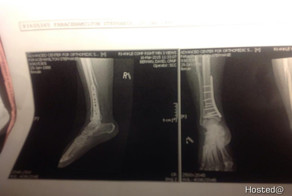

- Неудачное падение с переломом ноги